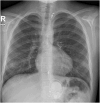

Results: The CardioMEMS device was implanted without technical complications in 8 pediatric patients (mean age 7 years and mean weight 27.9 kg) with pulmonary hypertension (6/8, 75%) and heart failure (2/8, 25%). The device was delivered via femoral access in 7 (85%) patients and implanted in the left pulmonary artery in 7 (85%). The noninvasive recording of pulmonary pressures in patients with pulmonary hypertension allowed the monitoring of the evolution of mean pulmonary artery pressure, intensifying vasodilator treatment, and avoiding control cardiac catheterizations. In patients with heart failure, pulmonary hemodynamic monitoring guided the decongestive treatment prior to heart transplantation.